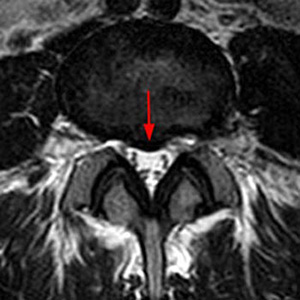

Every so often, though, a disc bulges or blasts out from a very far lateral standpoint, which will directly impact on either a right- or left-sided nerve in a very severe way. This is because  as the disc bulges out laterally, it hits the nerve as well as the surrounding bone and membrane, which leads to a very tight surface and volume for the nerve, resulting in  severe pain. In contrast to a standard lumbar disc herniation or sciatica, this will usually not respond to conservative measures such as physical therapy, medications, and/or epidural injections.

We recently had one such case of this uncommon occurrence in a 38-year-old bodybuilder who, after a particularly rigorous set of exercises over a month period, began having severe pain, numbness, and weakness into the left thigh region radiating from his back into his left knee.  He came in to see us at the Center for Musculoskeletal Disorders, and had an immediate MRI ordered showing a very large L2-3 far lateral disc herniation.  We attempted an epidural steroid injection to give him some relief, with the understanding that it may not give him the necessary long-term comfort and resolution